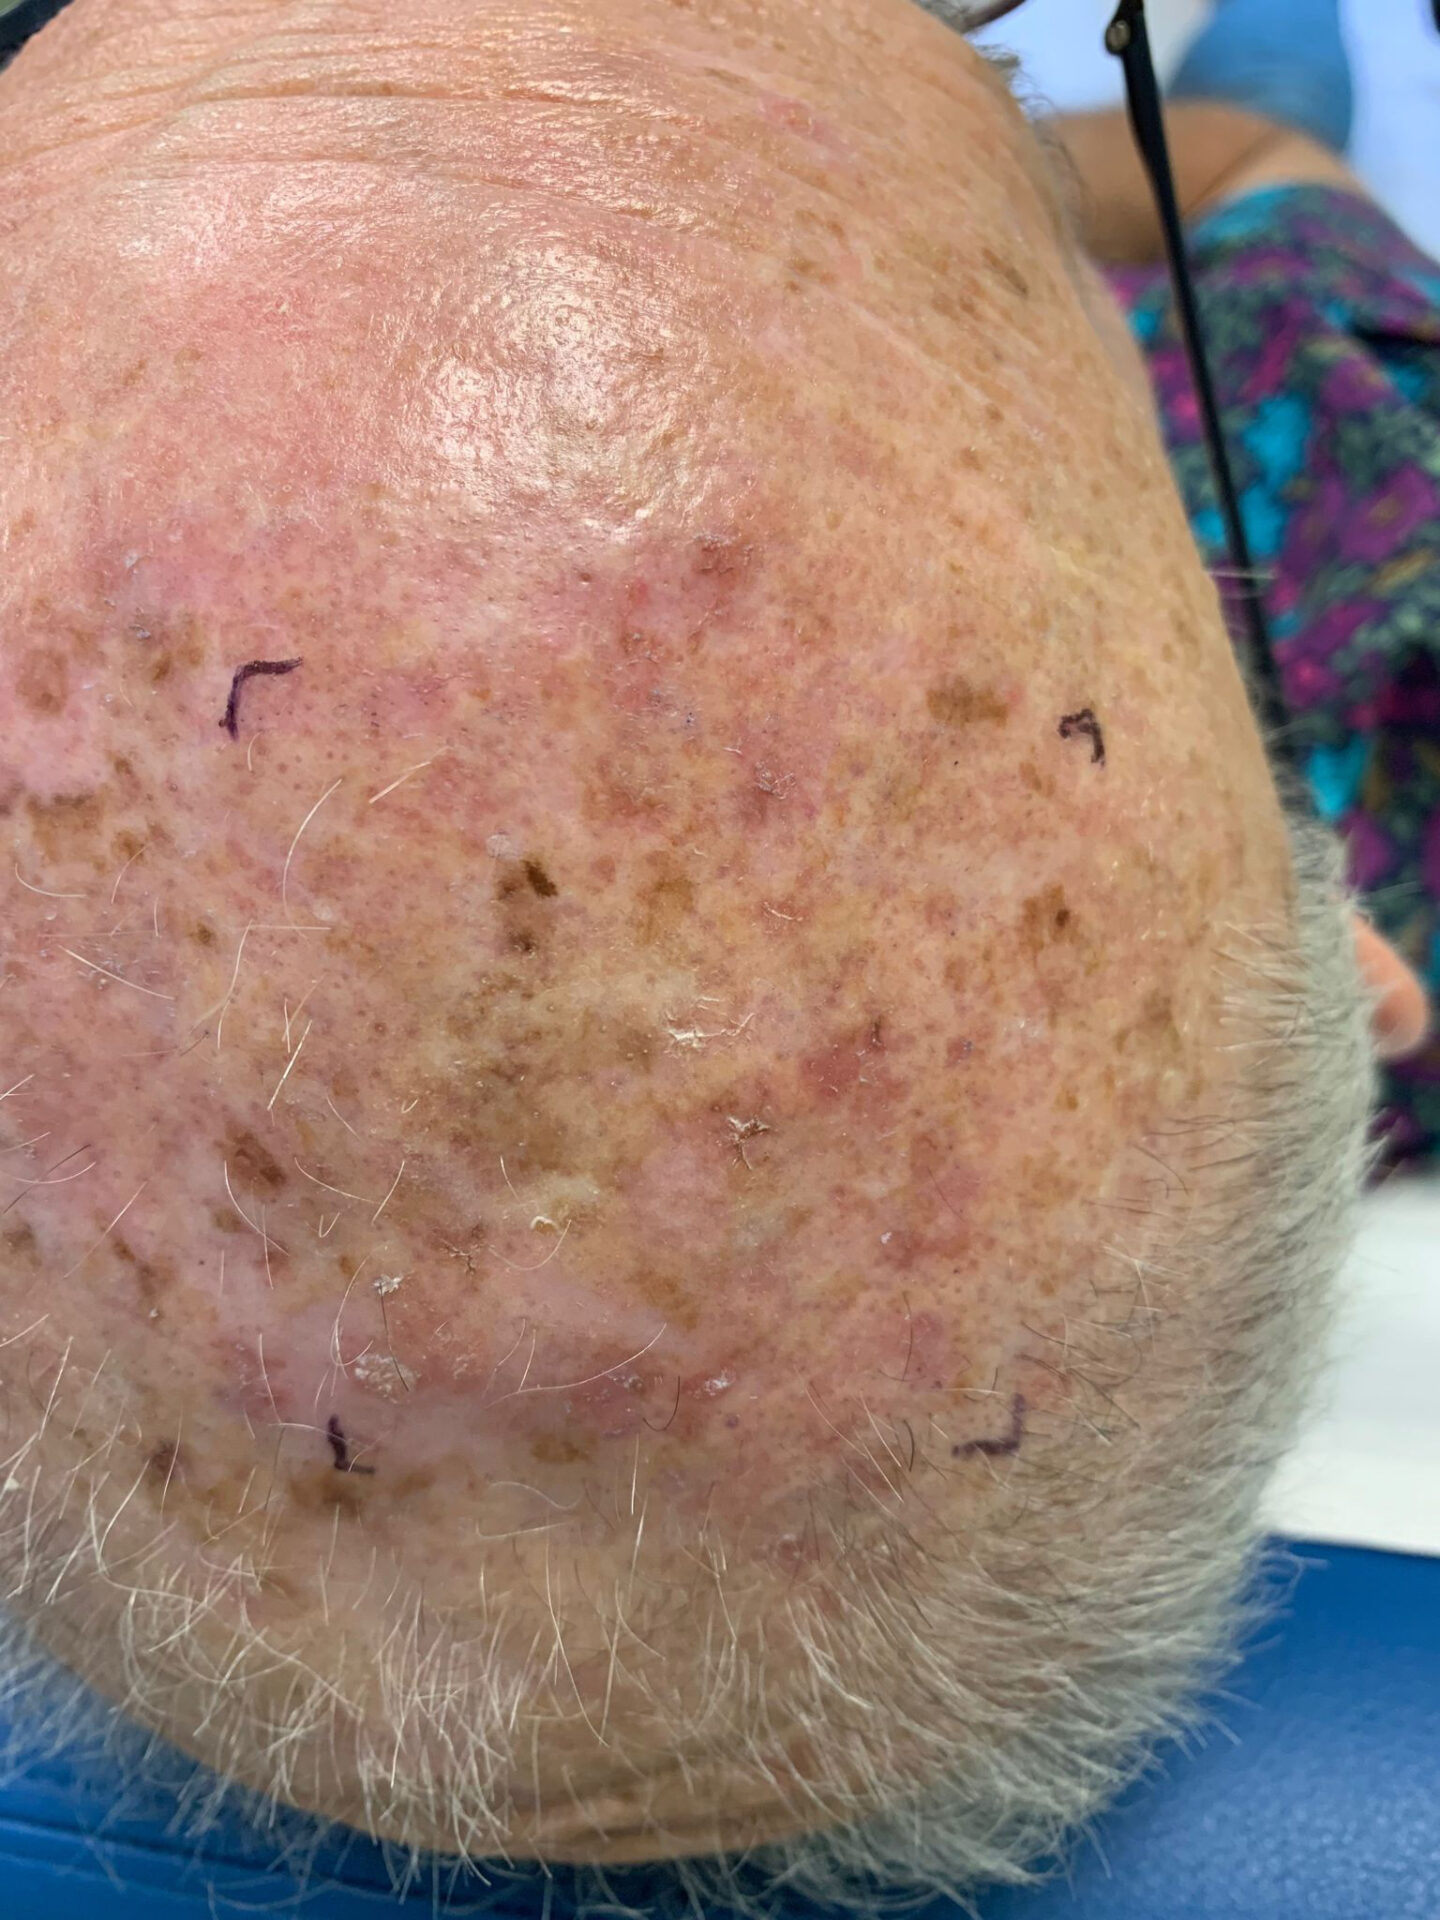

Squamous Cell Carcinoma (SCC) Photos

Squamous cell carcinoma on the head. Photo: International Skin Imaging Collaboration at isic-archive.com

Squamous cell carcinoma on the head. Photo: International Skin Imaging Collaboration at isic-archive.com